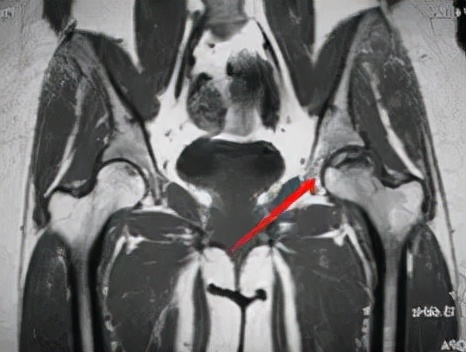

磁共振: 是一种有效的非创伤性的早期诊断方法。

大多表现为股骨头前上部异常信号:T1为条带状低信号;T2为低信号或内高外低两条并行信号影,即双线征(double line sign)。双线征中外侧低信号带为增生硬化骨质,内侧高信号带为肉芽纤维组织修复所致。